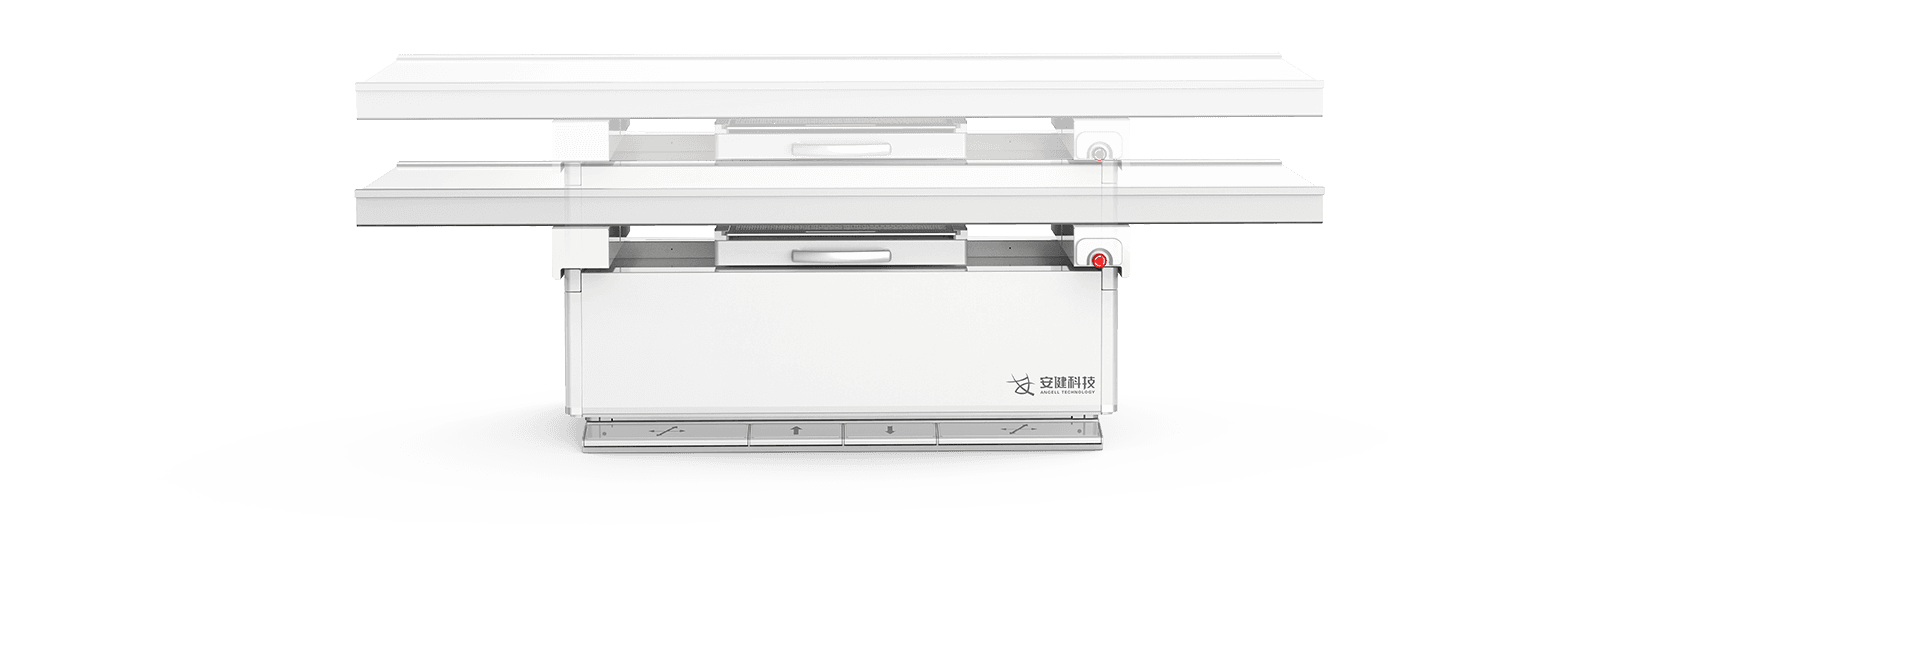

电动升降床

超大行程运动范围,灵活应对儿童、老人、外伤患者上下床。

配备嵌入式感应解锁系统,轻松调节床高并有效避免患者误触。